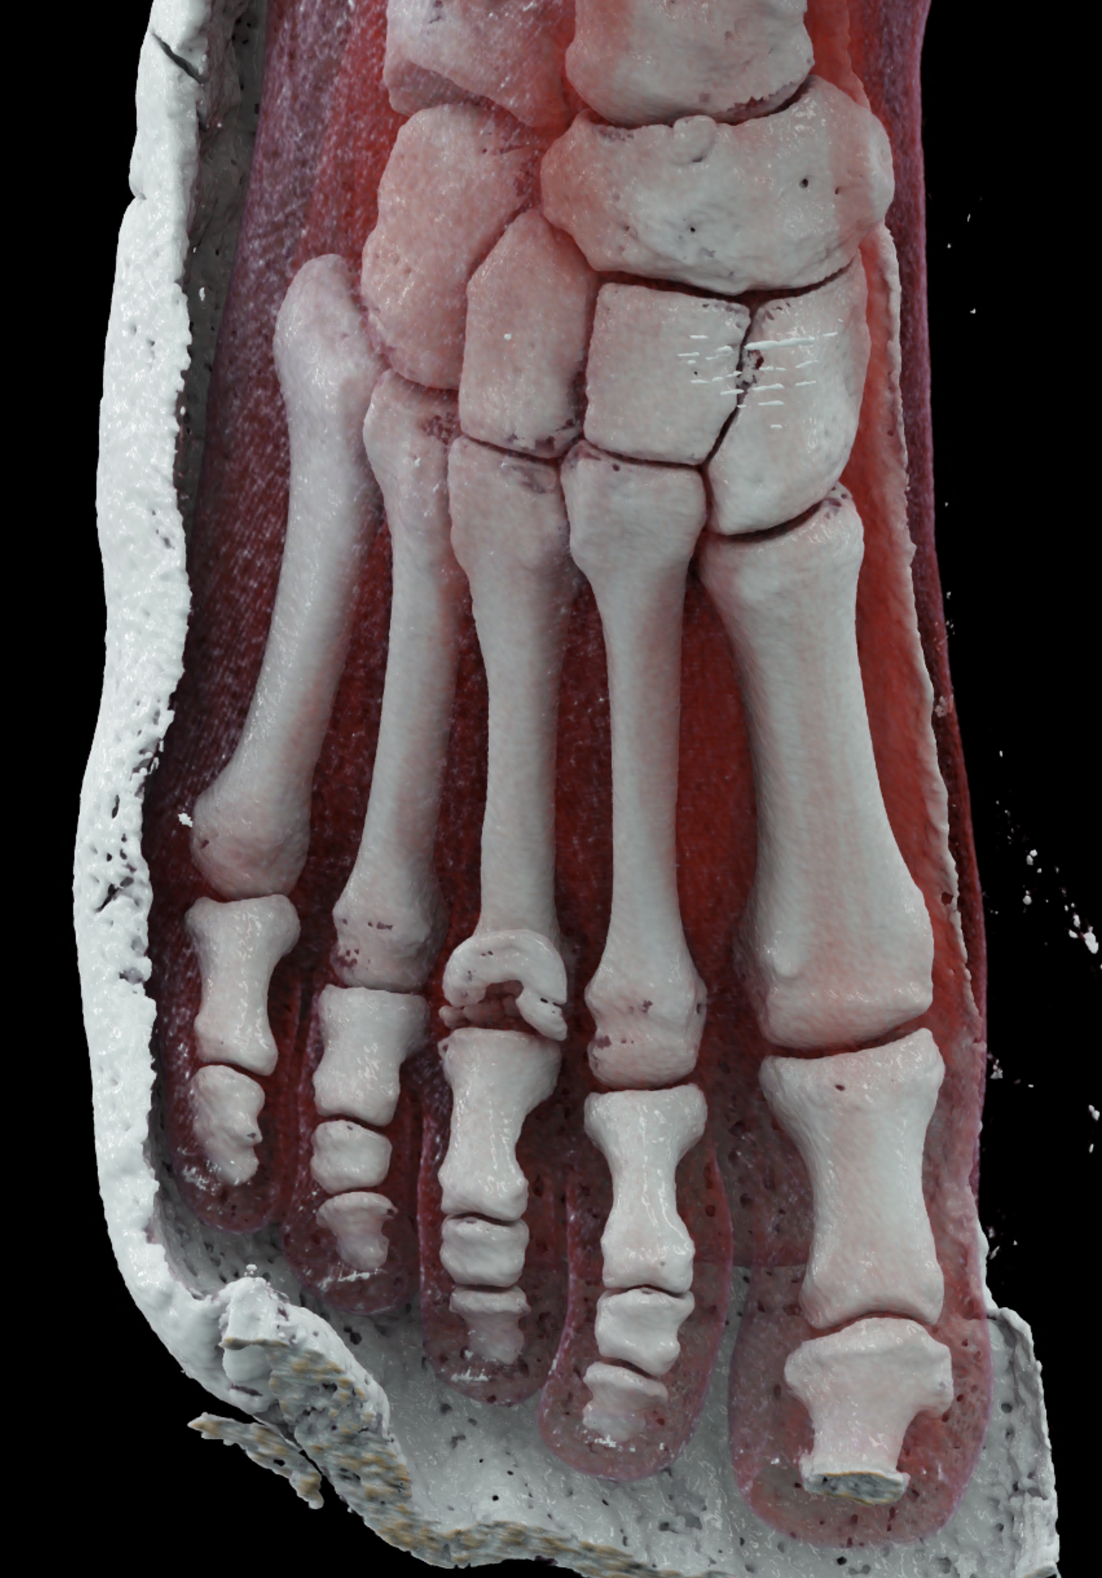

Freiberg-Koehler disease is aseptic necrosis of the head of the second or third metatarsal bone. It is more common in girls during puberty and skeletal maturation, when necrosis of the head occurs, followed by its fragmentation and subsequent deformity of the front part of the foot and the formation of pressure sores. In the acute stage, swelling and pain may occur in the area of the transverse flat arch of the foot. However, it very often progresses without any symptoms and only begins to manifest itself at a later age in connection with transverse flatfoot, with pain and pressure sores under the metatarsal heads in the front part of the foot. In the acute stage in growing children, pain in the front of the foot usually occurs after and following exertion. CT scans show fragmentation and dorsal subluxation of the distal fragments in aseptic necrosis of the metatarsal head more clearly than plain X-rays. Necrosis manifests itself in a changed structure and, in later stages, a significant change in shape; often, significant destruction of the metatarsal head can be seen.

When using ultra-high resolution CT with the smallest possible detector element, even the smallest details of bone changes can be visualized using photon-counting CT. By reconstructing images with a width of 0.2 mm and an overlap of 0.1 mm, there is a significant improvement in resolution in the planes of the reconstructed images in the metatarsal axis in the long axis of the foot, but also in the plane perpendicular to it, which better displays the metatarsophalangeal joint in the laterolateral direction.

volume rendered reconstructions